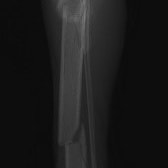

症例3:キルシュナーワイヤーのピンニングによる整復

ペルシャ猫 11ヶ月齢 雄

他院にて左大腿骨遠位の成長板骨折(salter-harrisⅠ型)が認められており、治療相談を目的として来院。当院にて、キルシュナーワイヤーを用いたピンニングにより骨折部位の整復を行いました。術後の経過は良好で、現在も経過観察中です。

術前レントゲン

術後レントゲン